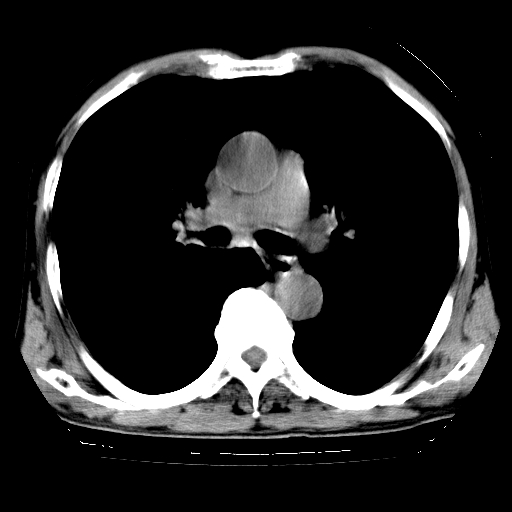

以下是引用hhcckk在2009-1-1 15:38:00的发言:[br]左下肺少许絮状模糊影--考虑感染[br]两肺散在小点状密度增高影--结合病史考虑矽肺?[br]气管壁钙化--可能由于老年退变性引起的